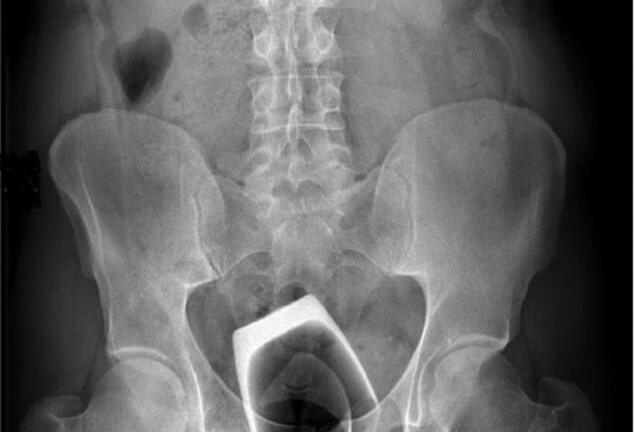

Hy hữu: Hình chụp X-quang phát hiện cốc uống rượu trong hậu môn

Một người đàn ông người Ý đã may mắn không bị mắc phải những chấn thương nghiêm trọng sau khi ông ta cố nhét một cái cốc uống rượu vào hậu môn để tăng cảm giác tình dục.